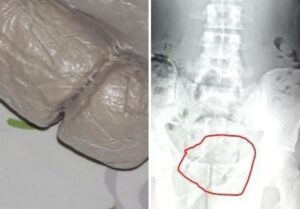

2 އަހަރު ކުރިން މާފުށީ ޖަލުގައި ބަންދުކޮށްފައި ހުއްޓާ ދަންޖެހިގެން މަރުވެފައި އޮއްވައި ފެނުނު މީހާގެ ހަށިގަޑު ޕޯސްޓު މޯޓަމް ހަދަން ފޮނުވައިފި